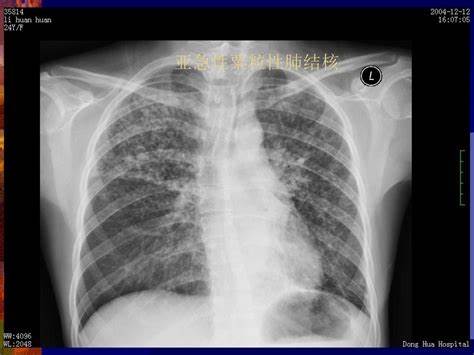

肺结核是由结核分枝杆菌引起的传染病,主要通过空气、飞沫经呼吸道传染。

肺结核多表现为慢性病程,症状有时候很不典型。如果在患者的痰或病理策划中没有找到结核分枝杆菌,诊断有时候比较困难。

因此,肺结核的诊断分为三种:疑似诊断、临床诊断和病原学诊断。

诊断需要从三个方面着手:流行病学依据,临床表现(包括收集到的症状,和检查到的体征),辅助检查结果(其中以痰检为最重要)。

- 胸部影像学检查显示与活动性肺结核相符的病变。

- 胸部影像学显示与活动性肺结核相符的病变,患者有咳嗽、咳痰、咯血等肺结核的可疑症状。

- 胸部影像学检查显示与活动性肺结核相符的病变,PPT试验强阳性或γ-干扰素释放试验(又叫T-SPOT)阳性。

- 胸部影像学检查显示与活动性肺结核相符的病变,经过诊断性抗菌治疗两周无效,或随访检查可以排除其他原因导致的肺部疾病者。